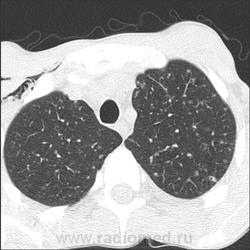

КТ с интервалом 20 дней от последнего снимка легких:

"Милиарные" очаги, а на верхушках - 1 скан - бяки.

На верхушках несколько очагов с кавитациями, до 10 мм диаметром. Остальные, преимущественно в верхних отделах, 2-4 мм.

Контакты профильные, "наркомовские". В мокроте ничего. Вчера КТ, вчера фтизиатр повторно, вчера без сомнений пациента забрали в ПТД, где сделана обычная обзорная рентгенография легких. Фтизиатр по телефону: милиарной диссеминации на снимке пока не видно.

Спасибо! Дело в том, что у нас уже такое бывало не раз: сначала на рентгенограммах чисто, а потом диссеминация. Инфекционист потому и назначил КТ, что подозревал, что высыпет туберкулез. А вот КТ лёгких ВИЧ-инфицированным проводим нечасто, такая микрокавитация вообще впервые попалась.

а мне кажется абсолютно не нормальные легкие , обогащенный рисунок, явно есть какая- то диссеминация , на верхушках очаги , плевропульмональные спайки и тд . что за воздух в мягких тканях ? а где изображения в сосудистом окне, может там куча лимфоузлов в средостении......

Что-то я потеряла нить повествования, запутавшись в комментариях). Уважаемые коллеги, по снимкам мной и моим коллегой выставлена норма. По КТ я выставила диссеминированный туберкулез легких. Лимфаденопатии средостения нет: короткий поперечник до 1 см, форма бобовидная (была б, я б показала в мягкотканном окне).